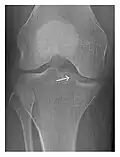

Occult osseous injuries may result from a direct blow to the bone by compressive forces of adjacent bones against one another or by traction forces during an avulsion injury. Lesions in the tibial plateau, hip, ankle, and wrist are often missed. In a tibial plateau fracture, any disruption of the posterior and anterior cortical rims of the plateau should be sought. Impaction of subchondral bone will appear as an increased sclerosis of the subchondral bone (Figure 1). In the hip, posterior acetabular fractures also present subtle radiographic findings. The acetabular lines should then be carefully examined keeping in mind that the posterior rim, which is harder to see on X-rays, is more frequently fractured than the anterior rim (Figure 2). In the wrist, detection of carpal bone fractures is often challenging, with up to 18% of scaphoid fractures radiographically occult. Carpal fractures, especially the scaphoid, are associated with the risk of avascular necrosis. In apparently normal wrist radiographs from symptomatic patients, if there is history of a fall on an outstretched hand with pain in the anatomic snuffbox, suggesting scaphoid injury, the initial examination with posteroanterior, lateral, and pronation oblique views must be complemented by other specific views such as supination oblique and the "scaphoid" view A careful examination of cortices for evidence of discontinuity or offset and cancellous bone for lucency is necessary (Figure 3).[1]

Figure 1: A 56-year-old woman presenting with left knee pain after a fall. (a) Initial anteroposterior radiograph was considered normal, however, subtle cortical disruption of the anterior rim of the medial tibial plateau, medial to the tibial spine, is noted (arrow). (b) Coronal T1-weighted MRI confirms the cortical disruption (arrow) and shows extensive fracture through the proximal tibia. (c) Coronal proton density-weighted image with fat saturation shows extensive edema in the subchondral bone. Note also hypersignal adjacent to the medial collateral ligament corresponding to a grade I sprain (arrowheads).[1]